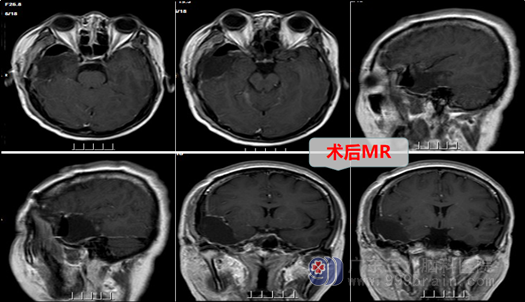

神经外十科欧阳辉教授接诊了张某,在了解详细病情后,结合患者外院MR,初步考虑“右侧颞叶肿瘤性病变”,欧阳教授向患者及其家属耐心解释病情及其预后,在征得患者及家属同意后,外十科团队在全麻下行右侧题叶低级别胶质瘤切除术+硬脑膜补片修补术+颅骨骨瓣修补术;全切肿瘤,手术顺利。术后患者神志清楚,病理诊断为:神经原性一级肿瘤(良性),患者术后也没有出现后遗症。